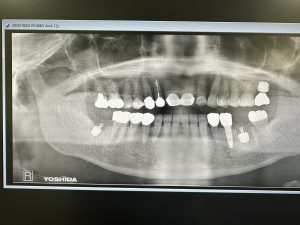

本日は午前、午後とインプラントオペあり

お二方共に浅草橋時代からの患者さん🙏